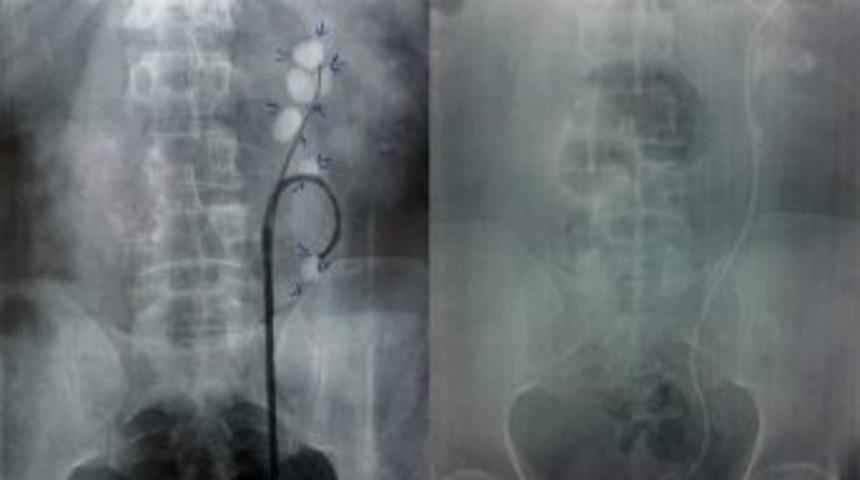

Menekşe yaptığı açıklamada, "Daha önceleri açık ameliyatla tedavi edilen böbrek taşları, minimal invaziv olarak nitelenen, en az zarar veren ve en çabuk günlük hayata dönüşü sağlayan ameliyat yöntemleri ile tedavi edilebilir hale gelmiştir. Bu yöntemlerin sonuncusu ve en moderni Lazer'in kombine edildiği son teknoloji, fleksible, endoskopik cihazların kullanıldığı RIRC olarak tanımlanan Retrograd Intarenal Cerrahi yöntemidir" dedi.

Menekşe açıklamasında şunları söyledi: "İdrar yollarında hareketli ve kıvrılabilen bir kamera yardımıyla böbreğe girilip, böbrek içerisindeki taşlar ve tümörlerin tespit edilmesi, aynı anda holmium lazer ile taşların böbrek içinde kırılması veya eritilmesi ile taş tedavisi yapılabilmektedir. Herhangi bir kanama olmadan tamamlanan tedavinin ardından hastalar çok kısa sürede taburcu ediliyor."